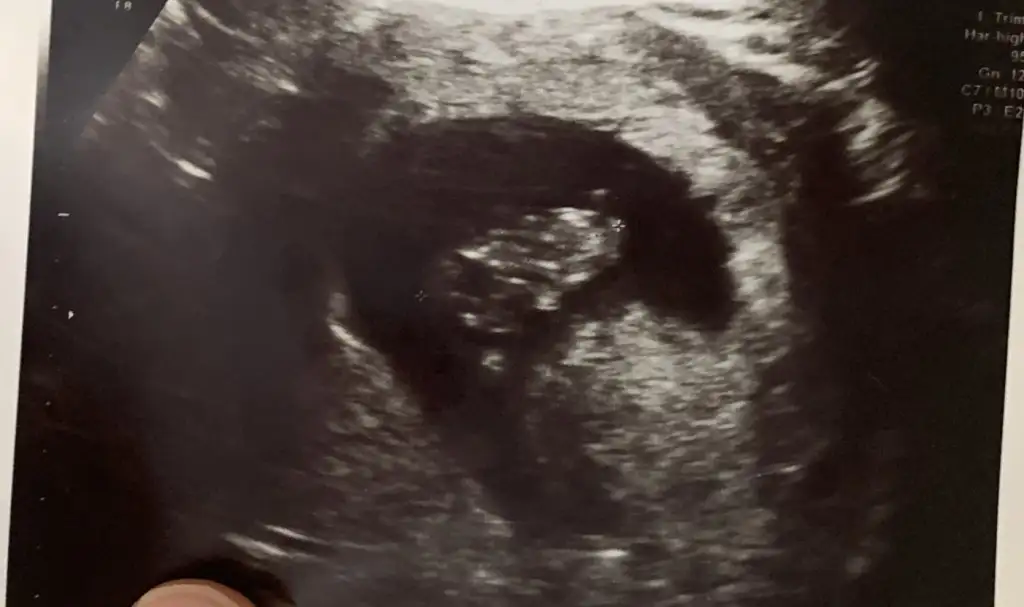

Kızlarrr burda bebeğimin başı ve poposu nerde kalıyor acaba doktor gösterdi ama ben anlamadım, bir de plasenta oluşmuş dedi açıklayabilir misiniz rica etsem, 9 haftalık gebelik ultrasonu bu

B beyzadz Yeni Üye Kayıtlı Üye 22 Şubat 2023 38 13 3 28 26 Nisan 2023 Konu Sahibi Konu Sahibi beyzadz #3 Lmntbrdgi .!.: İki nokta arası Genişletmek için tıkla... İki nokta arası olduğunu biliyorum başı hangi tarafta poposu hangi tarafta onu sordum anlayamadığım için

Lmntbrdgi .!.: İki nokta arası Genişletmek için tıkla... İki nokta arası olduğunu biliyorum başı hangi tarafta poposu hangi tarafta onu sordum anlayamadığım için